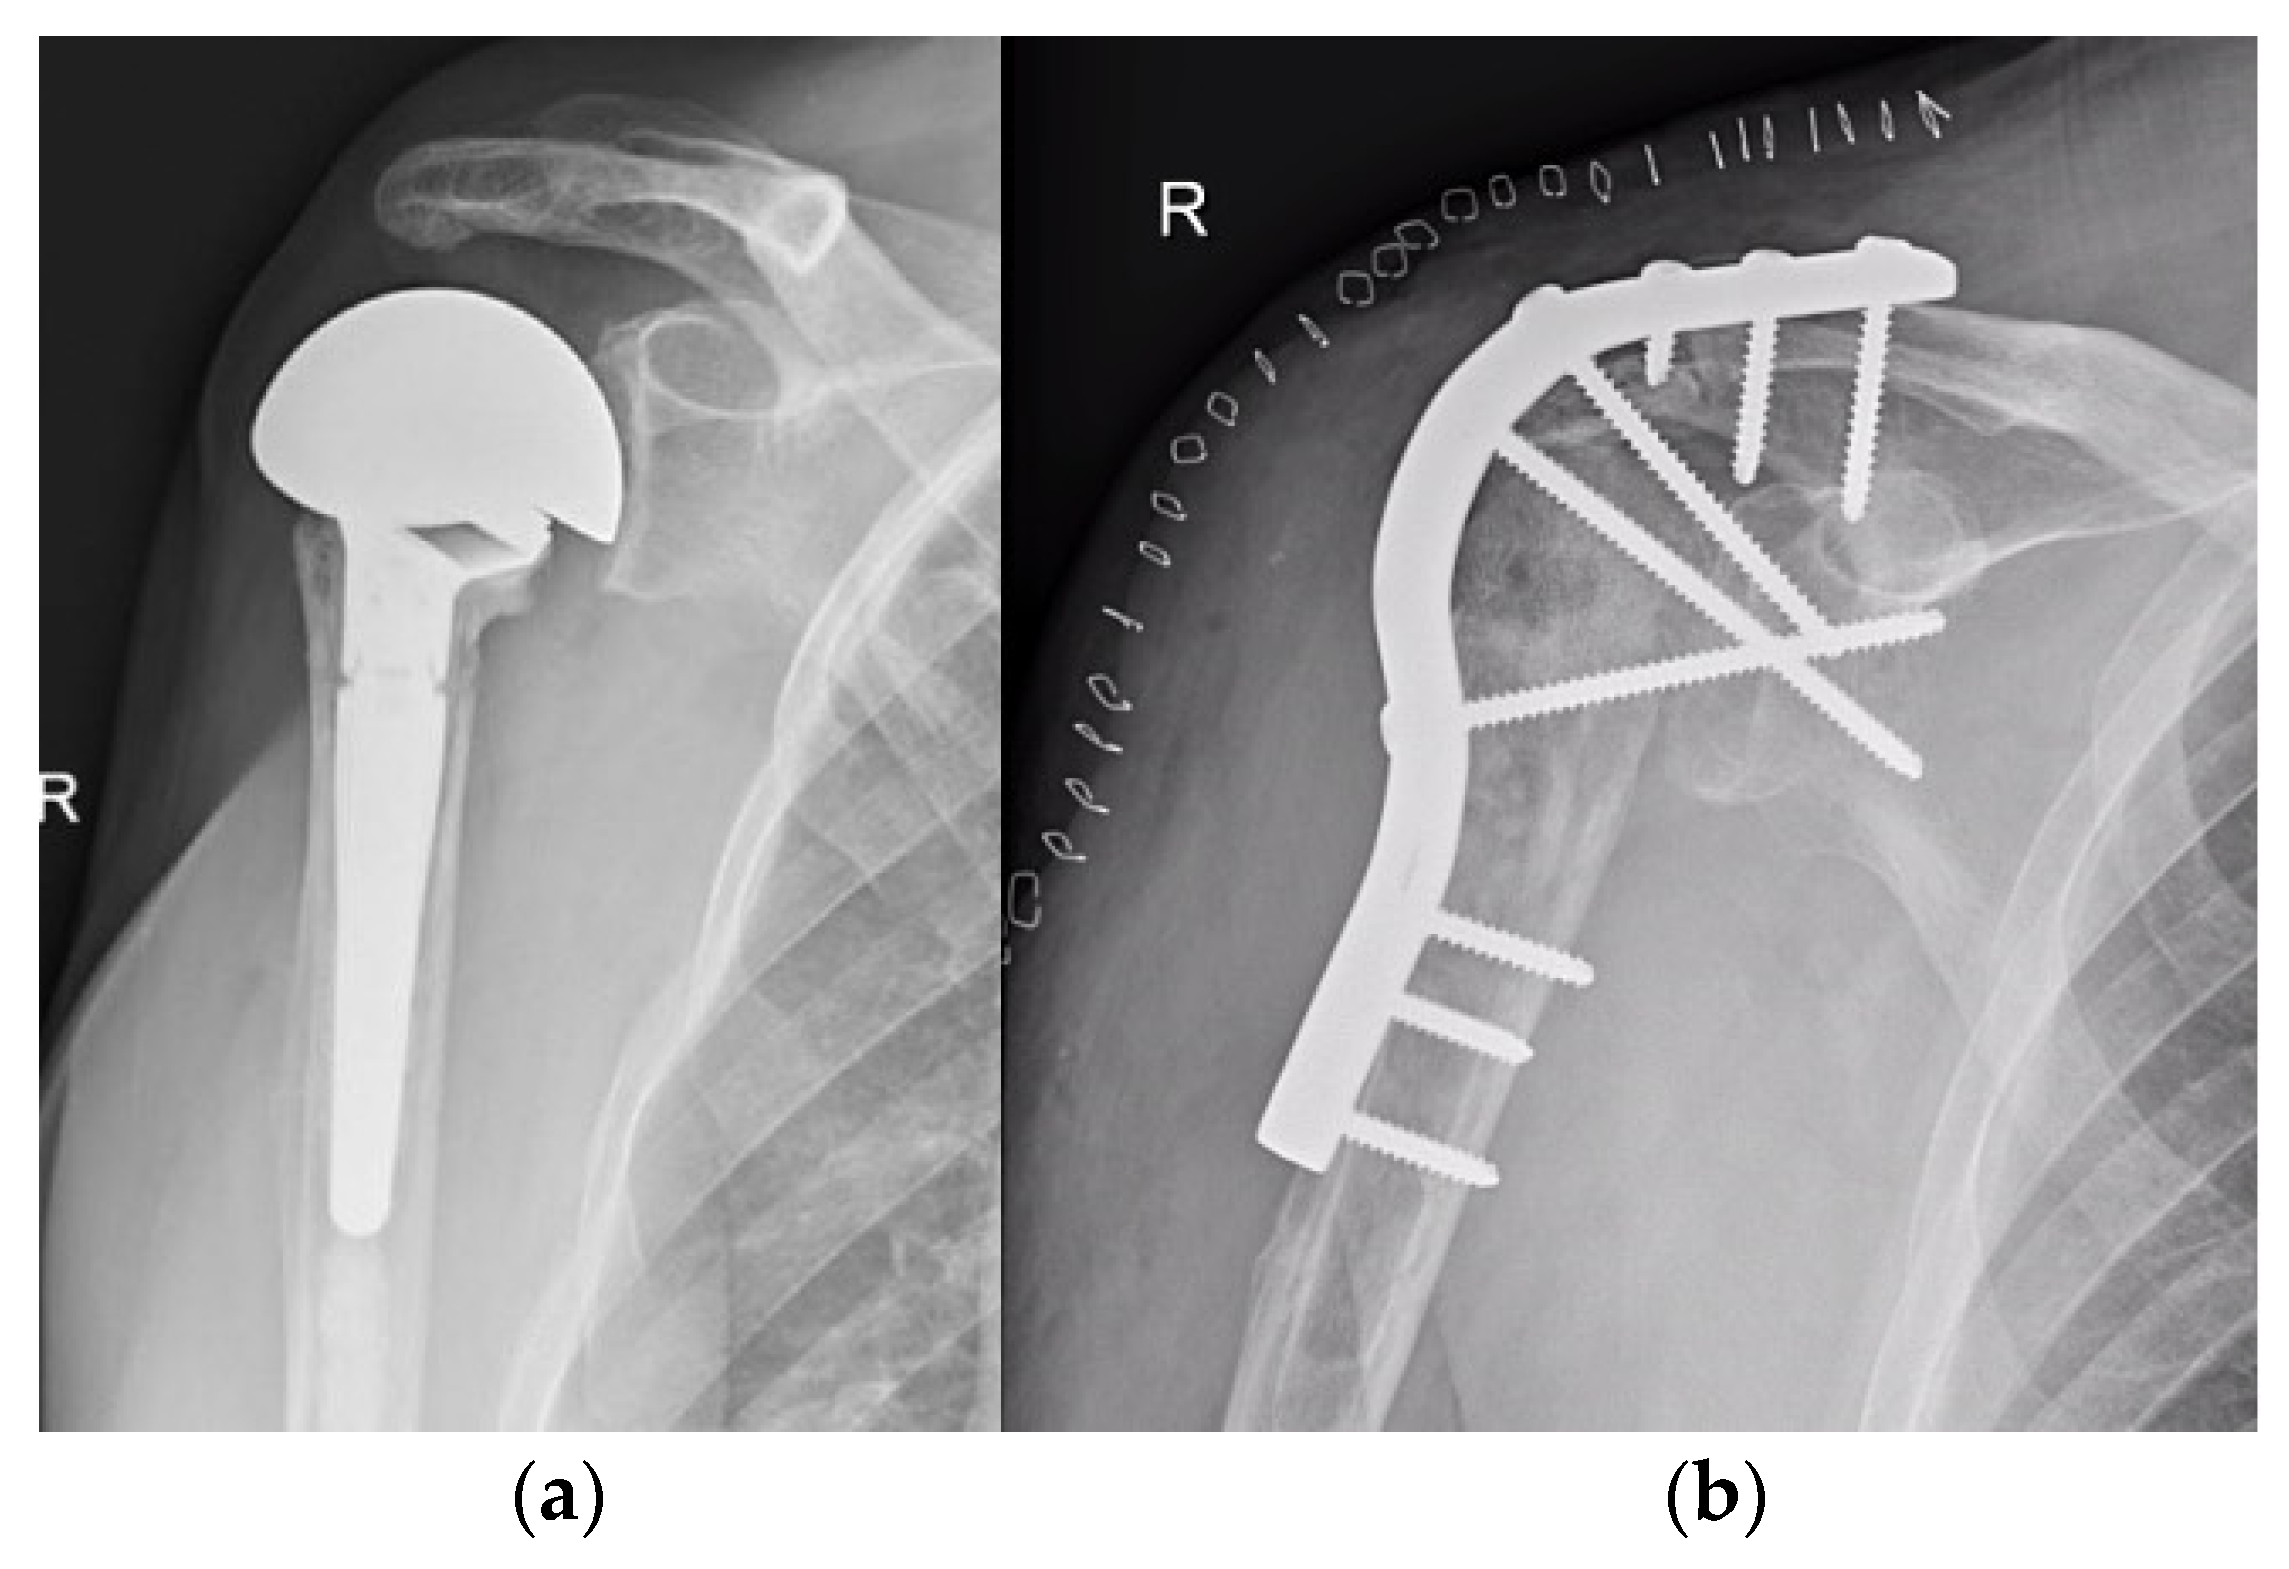

4.2. Shoulder

4.3. Elbow

- Kamineni, S.; Unger, R.Z.; Desai, R. Shoulder Arthrodesis in the Management of Glenohumeral Pathologies. J. Shoulder Elb. Arthroplast. 2019, 3, 2471549219850655. [Google Scholar] [CrossRef]

- Porcellini, G.; Savoie, F.H.; Campi, F.; Merolla, G.; Paladini, P. Arthroscopically Assisted Shoulder Arthrodesis: Is It an Effective Technique? Arthroscopy 2014, 30, 1550–1556. [Google Scholar] [CrossRef] [PubMed]

- Mattei, L.; Mortera, S.; Arrigoni, C.; Castoldi, F. Anatomic Shoulder Arthroplasty: An Update on Indications, Technique, Results and Complication Rates. Joints 2015, 3, 72–77. [Google Scholar] [CrossRef]

- van den Bekerom, M.P.J.; Geervliet, P.C.; Somford, M.P.; van den Borne, M.P.J.; Boer, R. Total Shoulder Arthroplasty versus Hemiarthroplasty for Glenohumeral Arthritis: A Systematic Review of the Literature at Long-Term Follow-Up. Int. J. Shoulder Surg. 2013, 7, 110–115. [Google Scholar] [CrossRef] [PubMed]

- Chawla, H.; Gamradt, S. Reverse Total Shoulder Arthroplasty: Technique, Decision-Making and Exposure Tips. Curr. Rev. Musculoskelet. Med. 2020, 13, 180–185. [Google Scholar] [CrossRef]